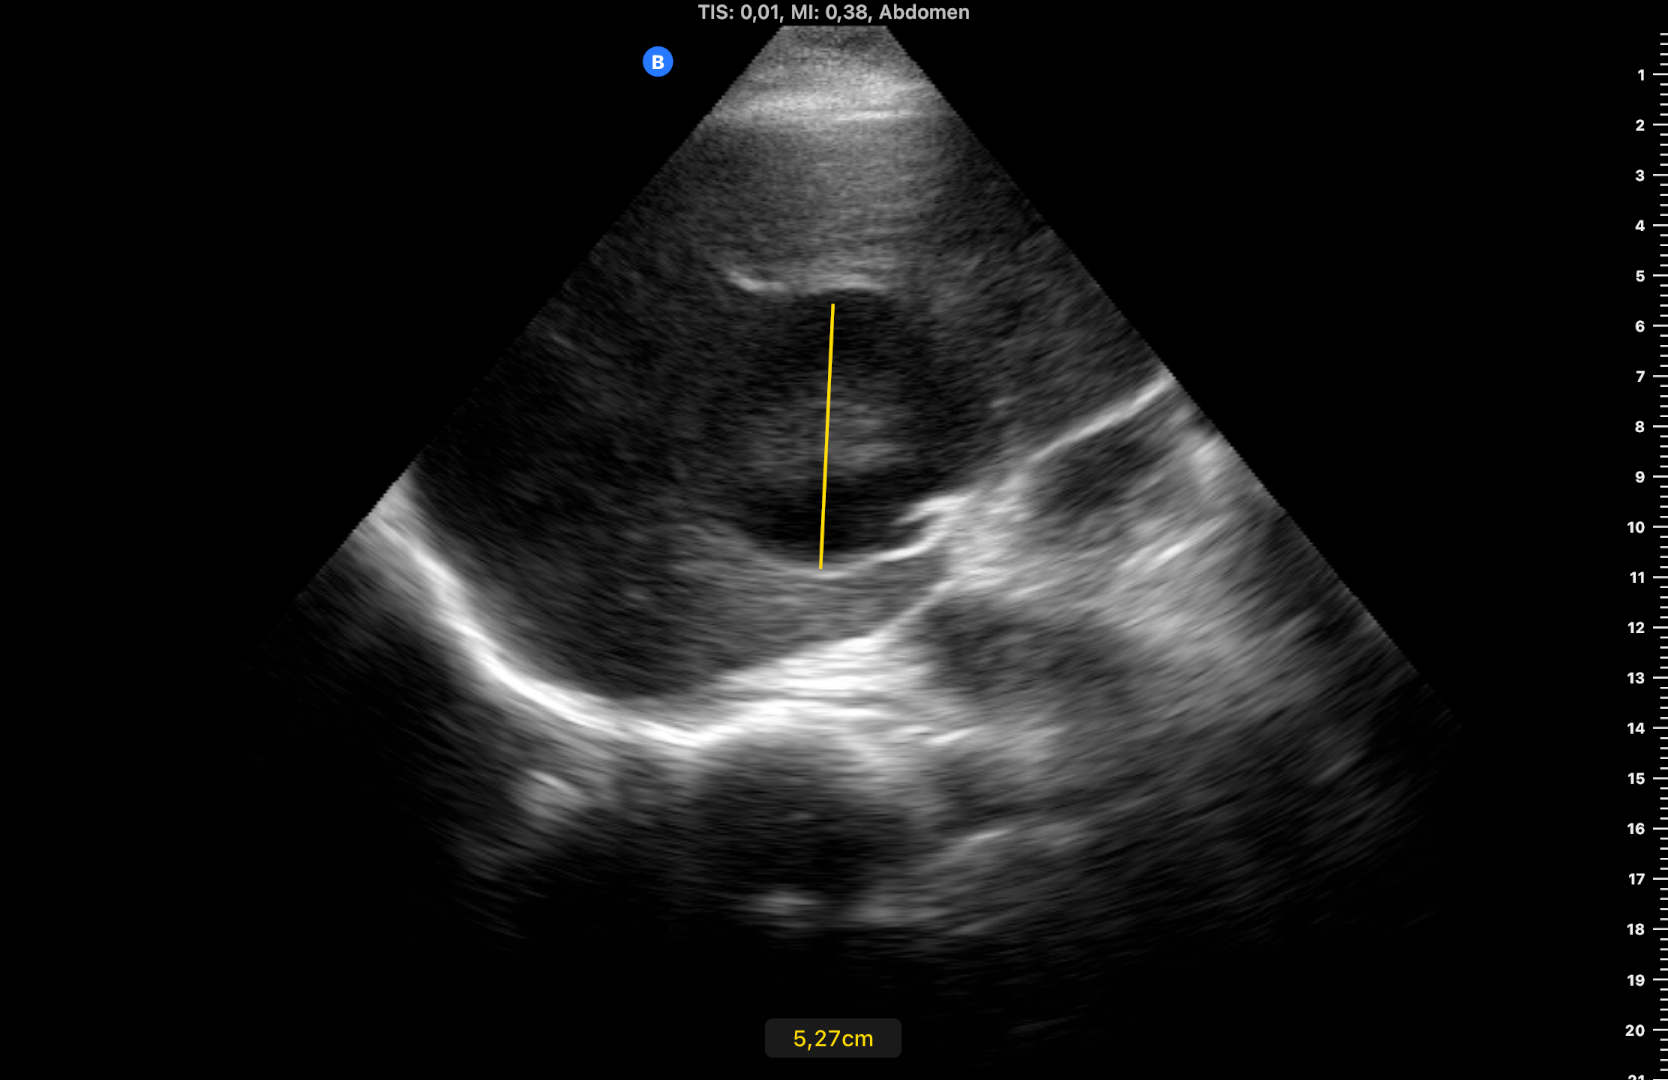

Ecografía inicial con ecógrafo portátil con múltiples LOES hepáticas hipoecogénicas de 5-6 cm de diámetro, alguna con centro hiperecogénico (figuras 1 y 2), que se confirman con ecógrafo de consola (figuras 3 y 4) con flujo Doppler aumentado respecto al resto de parénquima (hay vídeos).